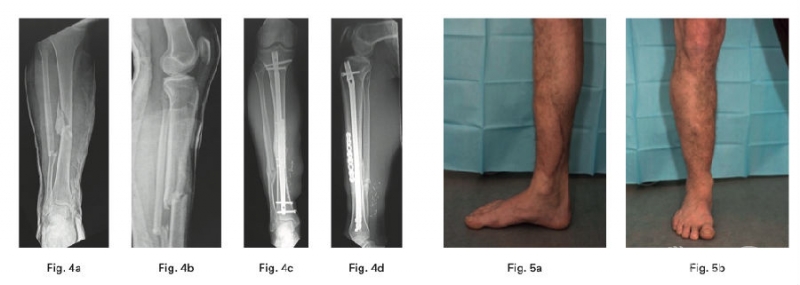

六、膝、小腿及踝部

胫骨平台骨折是过去二十年研究的热点,从分型到治疗有了成熟的研究和认识。而小腿骨折和足踝部骨折因大量的手术病例和并发症,始终是研究的一个热点。

2、Hourani AI在一项病例系列中确定了使用mechanically relevant devitalized bone (ORDB)进行矫形重建是否与IIIB型开放性胫骨干骨折感染率增加相关,其结论为在IIIB型开放性胫骨干骨折治疗的情况下,在最终重建中使用ORDB是安全的。